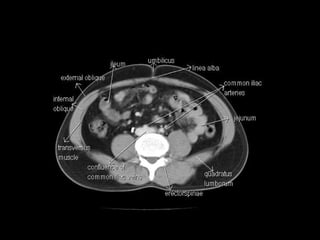

Radiographers use medical imaging equipment like X-rays and MRIs to produce images of patients' internal structures and organs. They are responsible for positioning patients, operating scanning machines, and ensuring quality images. Radiographers must have strong attention to detail, excellent communication skills, and the ability to work well under pressure to accurately capture anatomical features and diagnose any abnormalities.